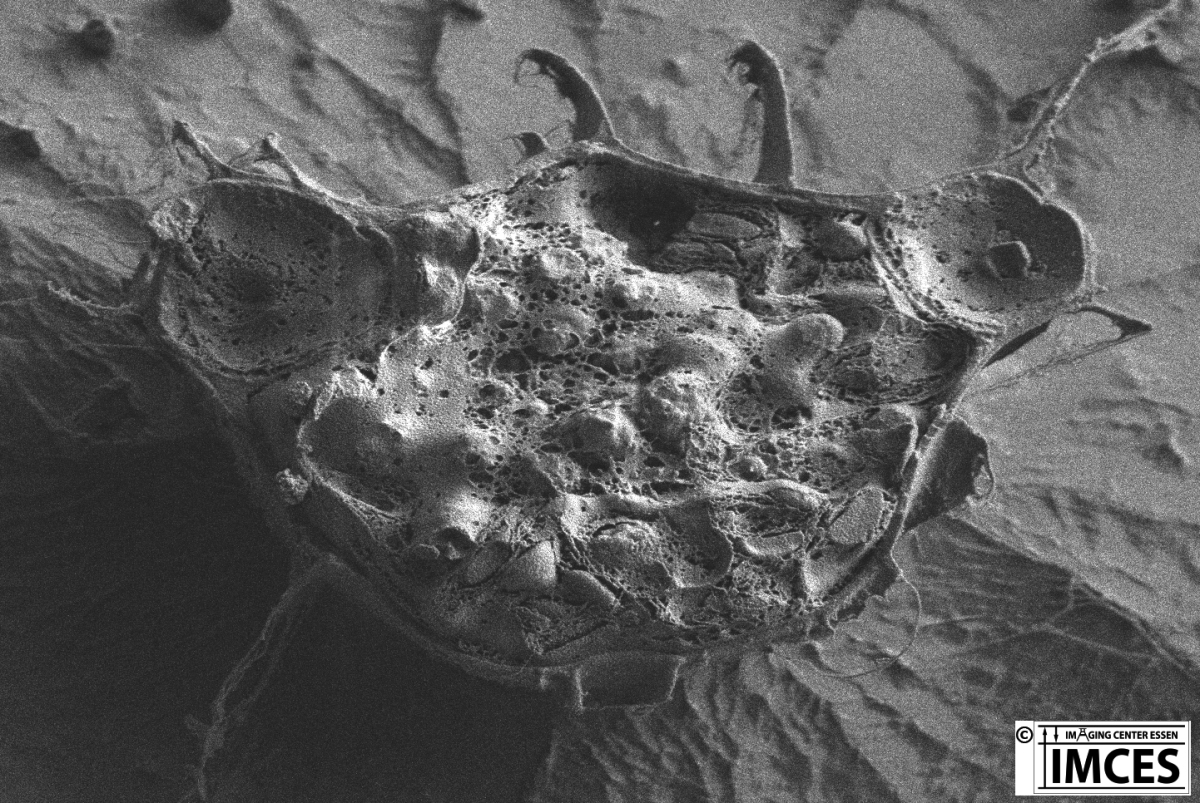

Bachelorarbeit J. Heinen-Weiler in Kooperation mit AG Prof. Gunzer, Institut für experimentelle Immunologie & Bildgebung Uni Duisburg-Essen Zeiss Crossbeam 540

Das nachkolorierte rasterelektronenmikroskopische Bild zeigt von neutrophielen Granulozyten ausgeworfene Netze in denen sich Bakterien verfangen haben.